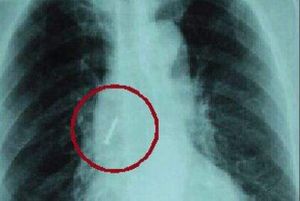

胸痛也是肺積水病的主要原因,但一般必須病變波及胸膜尤其是波及壁層胸膜,時可以出現胸痛。壁層胸膜即前面胸廓與肺臟的結核圖2、3中所示即為壁層胸膜。有時出現不定部位的隱痛,這是由於神經反射作用所致,在肺呼吸運動時不受影響。如果部位固定有刺痛,並隨呼吸及咳嗽時加重,這就說明炎症刺激胸膜所致,有的病人常感覺肩部或上腹部痛,這很可能是炎症刺激了橫膈膜通過神經反射所致。